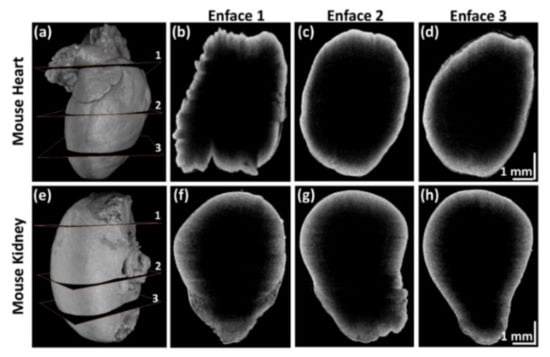

Figure 8 shows the 3D volumetric and enface images of mouse heart and kidney specimens acquired in sequential QS-OCT. Full-directional 3D rendering morphological images of the mouse heart and kidney are shown in Figure 8a,e, respectively. Every side of the sample was scanned vertically using a linear motor stage for volumetric imaging (1000 × 2048 × 725 pixels). Independently obtained volumetric images from four different sample arms were merged to obtain enface images with customized rendering software. Figure 8b–d,f–h are the representative enface images that were obtained from three different layers of 3D volumetric imaging of mouse heart and kidney specimens, shown in Figure 8a,e, respectively. The enface images shown in Figure 8b–d,f–h demonstrate the proper merging process for obtaining whole-directional volumetric data of the sample. The obtained 3D volumetric and enface images of the mouse heart and kidney specimens verify the whole-directional imaging capability of QS-OCT.

Figure 8.

3D volumetric and representative enface images of mouse heart and kidney using quad-scanner (QS)-OCT. (a,e) are full-directional 3D rendering morphological images of a mouse heart and kidney; (b–d) and (f–h) are the selected enface images obtained at the three different layers shown in (a,e), respectively.